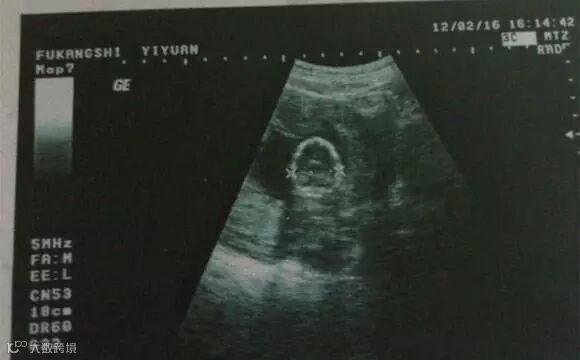

B超测怀孕

受精日45天以后才能测试

准确程度:★★★★★

B超是通过检测子宫内是否有孕囊来确认是否怀孕,跟检测HCG、孕酮等激素相比,B超测怀孕其实更直观更准确。这种检测方法要在受精日45天以后才能测试。

B超根据症状进行早孕的诊断标准率较高,是早孕临床诊断的有效方法。同时,B超还可以对胎儿的发育、胎盘的位置、羊水的多少、发育是否正常等做出相应的判断。